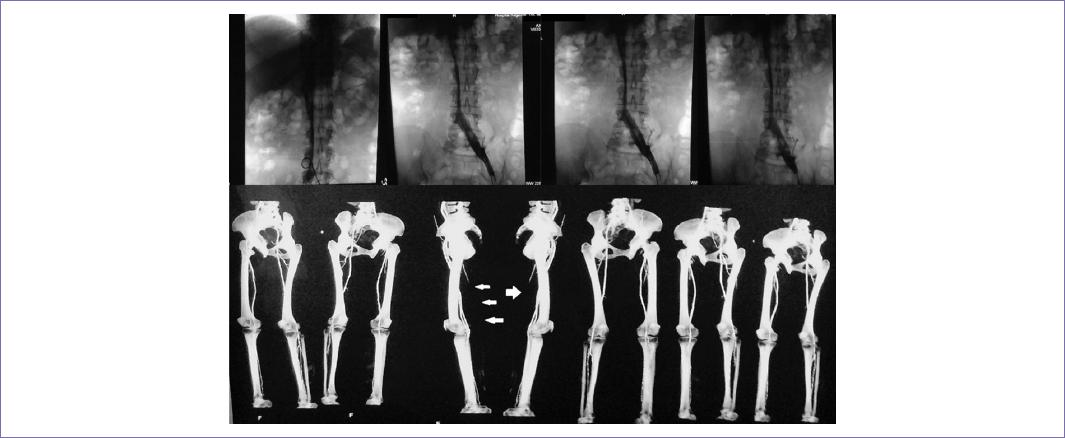

El US transvaginal reveló miomatosis uterina de medianos elementos de tipo intramural con degeneración cálcica; así como masa sólida retroperitoneal de forma piriforme con dimensiones de 95 x 37 mm; a la aplicación de US Doppler no hubo presencia de vascularidad. Conjuntamente le fue realizada una tomografía computarizada (TC) (Fig. 1) más venografía (Fig. 2), la cual mostró trombosis parcial de la vena cava inferior, desde la bifurcación de las venas ilíacas, hasta aferencia de venas suprahepáticas; por tal motivo, hubo necesidad de colocar un filtro en vena cava por encima de la aferencia de las venas renales.

Figura 2 Arriba, flebografía con medio de contraste en la cual se aprecia interrupción del flujo en vena ilíaca derecha, así como disminución de la luz en vena cava. Abajo, reconstrucción tridimensional mediante imágenes obtenidas por TC, que muestran paso irregular del medio de contraste por obstrucción a nivel de miembro inferior derecho.